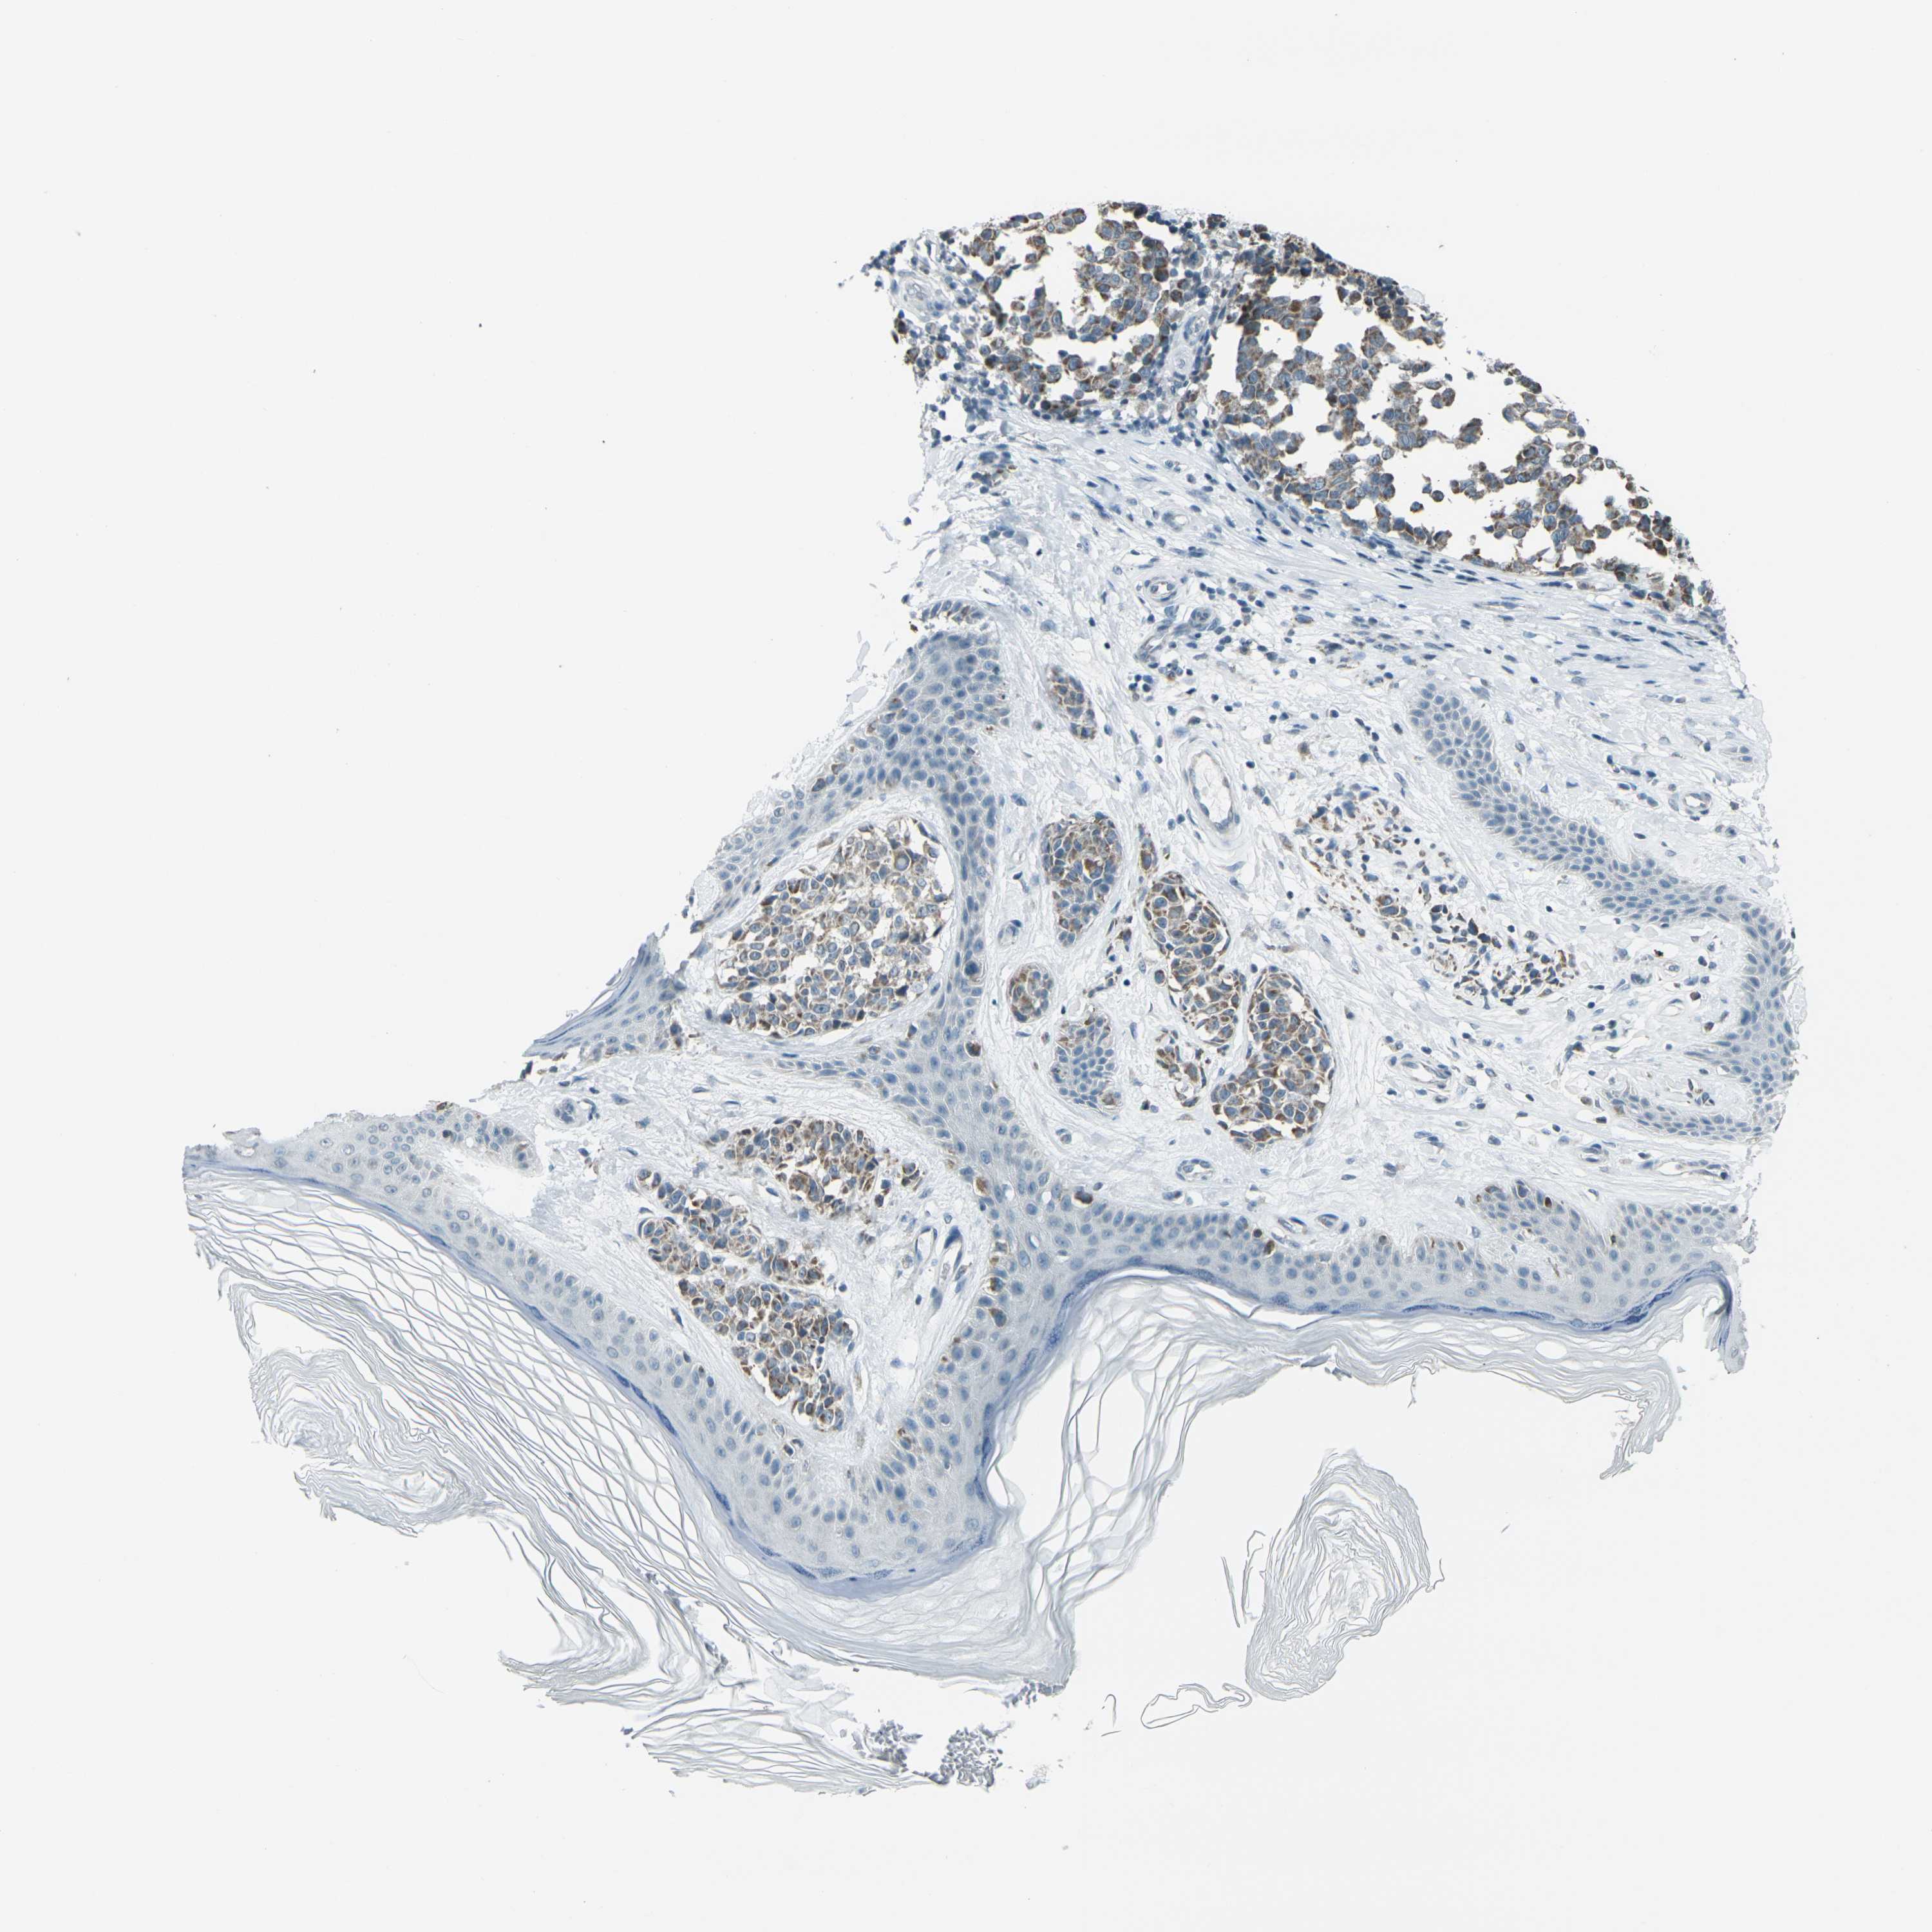

MELANOMA - Protein expressioni

A mouse-over function shows sample information and annotation data. Click on an image to view it in a full screen mode. Samples can be filtered based on level of antibody staining by selecting one or several of the following categories: high, medium, low and not detected. The assay and annotation is described here.

Note that samples used for immunohistochemistry by the Human Protein Atlas do not correspond to samples in the TCGA dataset.

Antibody stainingi

Antibody staining in the annotated cell types in the current human tissue is reported as not detected, low, medium, or high, based on conventional immunohistochemistry profiling in selected tissues. This score is based on the combination of the staining intensity and fraction of stained cells.

Each image is clickable and will lead to virtual microscopy that enables deeper exploration of all samples and also displays staining intensity scores, fraction scores and subcellular localization as well as patient and tissue information for each sample.

Antibody HPA042205

Antibody HPA043013

Antibody CAB011603

Staining

High

Medium

Low

Not detected

Intensity

Strong

Moderate

Weak

Negative

Quantity

>75%

75%-25%

<25%

None

Location

Nuclear

Cytoplasmic/membranous

Cytoplasmic/membranous,nuclear

Malignant melanoma, NOS

Malignant melanoma, Metastatic site

Malignant melanoma in situ